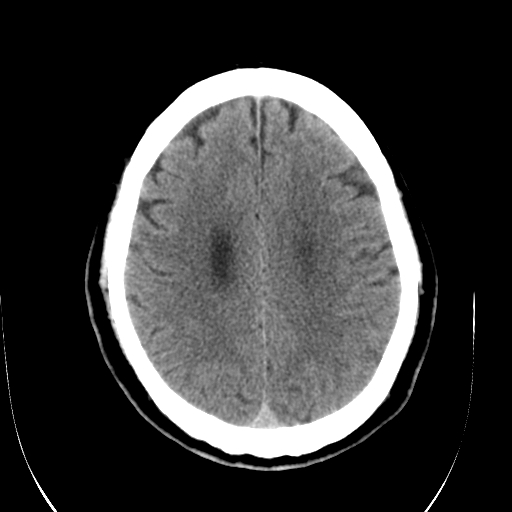

标题: CT28335:男,58岁,请各位看看是不是有脑积水,蝶窦内高密 [打印本页]

标题: CT28335:男,58岁,请各位看看是不是有脑积水,蝶窦内高密

轻度积水,蝶窦正常。

1)脑积水。2)副鼻窦炎。